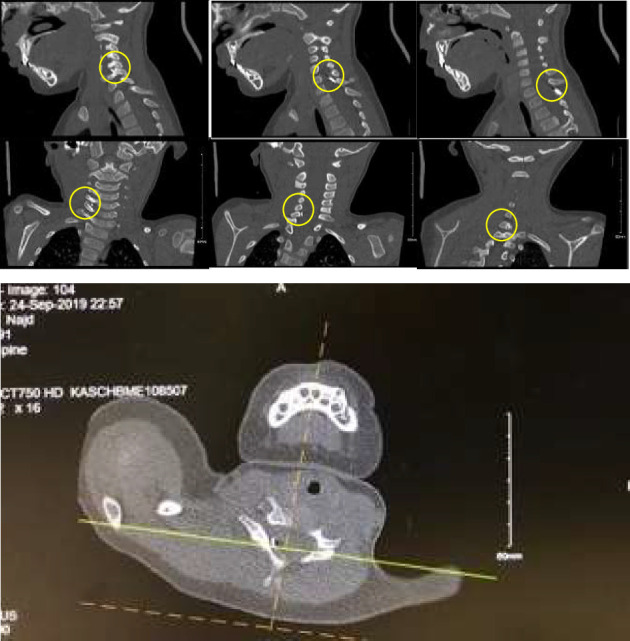

颈椎异物的病例被认为是罕见的,而针头移入椎管的病例是相当罕见的。记录最充分的案例是针灸针。我们报告一个2岁男孩的病例,偶然发现静脉注射针向后延伸至C7和T1棘间间隙,并在C5-C6间隙结束。我们讨论了可能的入境口岸和对这些发现的处理。

Cases of cervical foreign bodies are considered rare, and cases of needle that have migrated into the spinal canal are fairly uncommon. The most well-documented cases are those of acupuncture needles. We present a case of an incidental finding of an intravenous needle extending posteriorly between C7 and T1 interspinous space and ending at the level of C5-C6 interspace in a 2-year-old boy. We discuss the possible port of entry and the management of such findings.